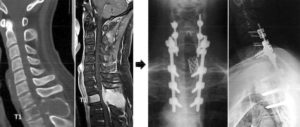

Лечение при трабекулярном отеке позвонков — операция по декомпрессии спинного мозга для восстановления его функции, насколько это возможно. Необходима послеоперационная реабилитация, поскольку при защемлении инвалидность неизбежна.

- мультиспиральную компьютерную томографию (МСКТ). При этом механизм томографа проходит вокруг пациента по спирали, делая снимки сразу в нескольких ракурсах. МСКТ является более современным способом обследования, чем обычная компьютерная томография, и применяется для диагностики позвоночника с целью дифференциации позвоночных грыж и опухолевых новообразований от отека костного мозга этого органа;